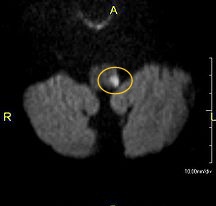

In our case, the MRI shows left lateral medullary infarct. So it manifests as loss of pain & temperature over the ipsilateral face and contralateral half of the body.